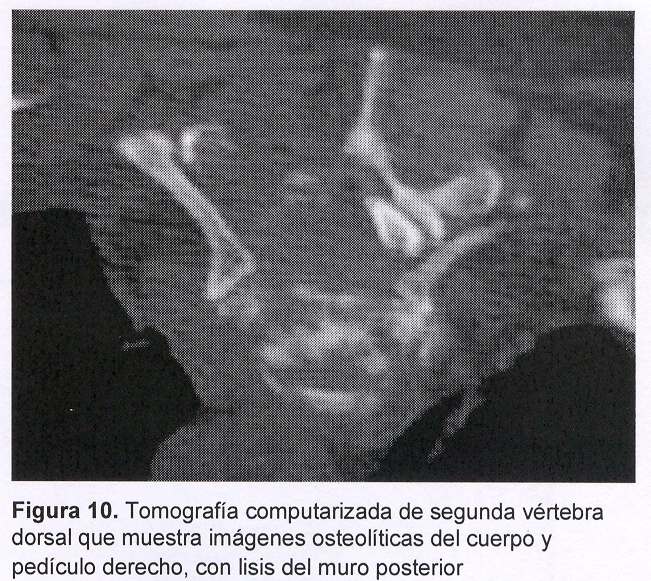

Sexo masculino, 58 años, con historia de dolor intenso raquídeo a nivel cérvico-dorsal, rápidamente progresivo, de dos semanas de evolución. Dos días previos a su ingreso instala síndrome radicular a nivel de T2 y T3. Se destaca la ausencia de signología medular. Al momento de la consulta con nuestro equipo, el paciente se encuentra con intenso dolor raquídeo cérvico-dorsal que le impide la deambulación. En los días previos comienza con aumento de la cifosis dorsal. Se realizó radiografía de frente y perfil y tomografía de columna cérvico-dorsal que mostraron: aplastamiento del cuerpo de T2 con aumento de la cifosis dorsal; sustitución parcial del cuerpo de T2 con lisis del muro posterior sin desplazamientos dentro del canal raquídeo (figura 10). Compromiso pedicular de T2 y de T3, principalmente a derecha.

Se decide realizar vertebroplastia percutánea de T2 por vía lateral derecha con control tomográfico durante la introducción del trocar en el cuerpo vertebral (figuras 11 y 12). El objetivo fue, entonces, disminuir el dolor, estabilización verterbral y toma de muestras de tejido tumoral para anatomía patológica.